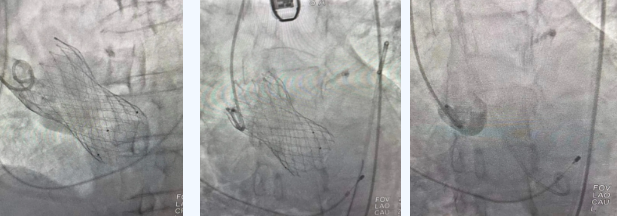

在麻醉手術(shù)中心的配合下,曾廣偉主任用導(dǎo)管經(jīng)股動脈鞘進(jìn)入主動脈瓣目標(biāo)位置,經(jīng)豬尾導(dǎo)管造影可見主動脈瓣大量返流,因左室流出道較寬,大于瓣膜落腳點直徑,瓣膜釋放位置選擇及釋放難度極大。更為關(guān)鍵的是,患者常規(guī)四個錨定點只有一個可以用,定位要極其精準(zhǔn)才能保證瓣膜釋放后牢靠,同時不能有大的殘余瘺!稍有移位可能就需要再次植入瓣中瓣或者開刀!

術(shù)中,曾廣偉主任團(tuán)隊高效配合,完成了特定時間點起搏心臟、臨時短時間關(guān)閉呼吸機(jī)、降低主動脈瓣阻力、快速釋放瓣膜等一系列高難度操作,有效保證瓣膜精準(zhǔn)釋放。瓣膜釋放經(jīng)TEE確認(rèn),主動脈瓣膜釋放位置佳,經(jīng)豬尾導(dǎo)管造影,主動脈瓣返流即刻消失,且無瓣周瘺。